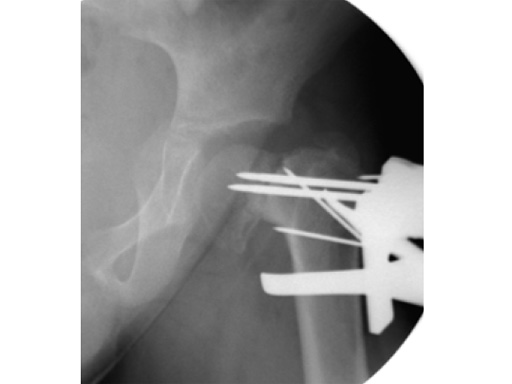

Case 2: LCP PHP 140. A 9-year-old boy, weighing 30 kg, had postinfectious pseudarthrosis of the femoral neck and varus deformity. His preoperative CC D angle was 80.

Case provided by Theddy Slongo, Bern, Switzerland